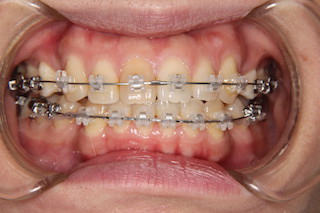

正面・・前歯も噛み合わせに参加です!

上顎・・前歯は少し下がりましたが、まだまだこれから

側面・・これから隙間を使ってもっと下げて行きます!